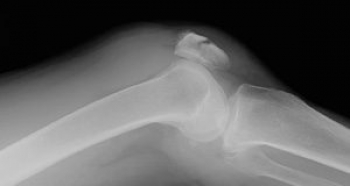

ɨ³¸¹ü¹üÀޤξɾõ

ɨ´ØÀá¤Î¼ðı¤ÈáÖÄˤ¬ÃøÌÀ

¹üÀÞÉô¤Î¸Â¶ÉÀ­°µÄË

ɨ³¸ç§Ëì¤ÎÃÇÎö¤ò¹çÊ»¤ò¤·¤Æ¤¤¤ë¤È¹üÀÞÉô¤ÎÎ¥³«¤ÈÈéÉæ¤Î´Ù±ú¤¬¿¨ÃΤ¹¤ë¡£

ľã³°ÎϤÏɨÁ°Ì̤ÎÈéÉæÂ»½ý

´°Á´¹üÀÞ¤Ïɨ´ØÀ῭ŸÎϤ˾㳲

ɨ³¸¹ü¤Î¹üÀޤϡ¢ËÜÅö¤ËÄˤ¤¤Ç¤¹¡Ê¤É¤Î¹üÀÞ¤âÄˤ¤¤Ç¤¹¤¬(*_*;¡Ë¡ª¡ª

¤½¤·¤Æ¡¢¤Û¤Ü¼ê½Ñ¡¡¼ê½Ñ¤¬Ë¾¤Þ¤·¤¤